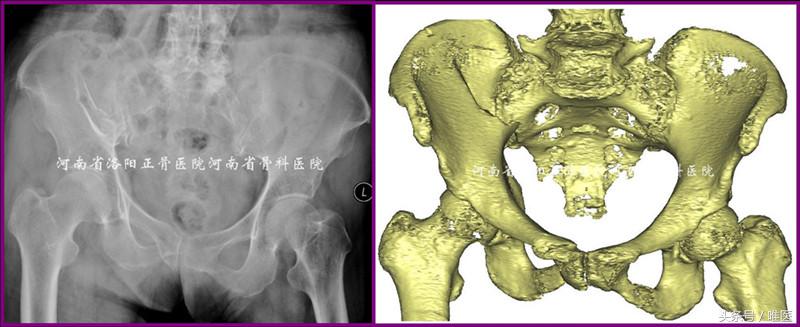

一例88岁女性病人因摔伤导致右半骨盆疼痛、右髋活动受限五天入院。其合并高血压病及心律失常。化验显示轻度贫血及低白蛋白,肝肾功能正常。彩超显示心脏功能正常,双下肢无静脉血栓形成。影像检查见图1。入院诊断:骨盆骨折(OTA-61B2.3):1.右侧髂骨新月形骨折;2.右侧耻骨上下支骨折。问:如何治疗?保守or手术?如手术,切开or闭合?每人都有自己的答案。但通过本期的讲解,相信大家会得出一个优选答案。

图1. 一例88岁女性骨盆骨折的影像资料。